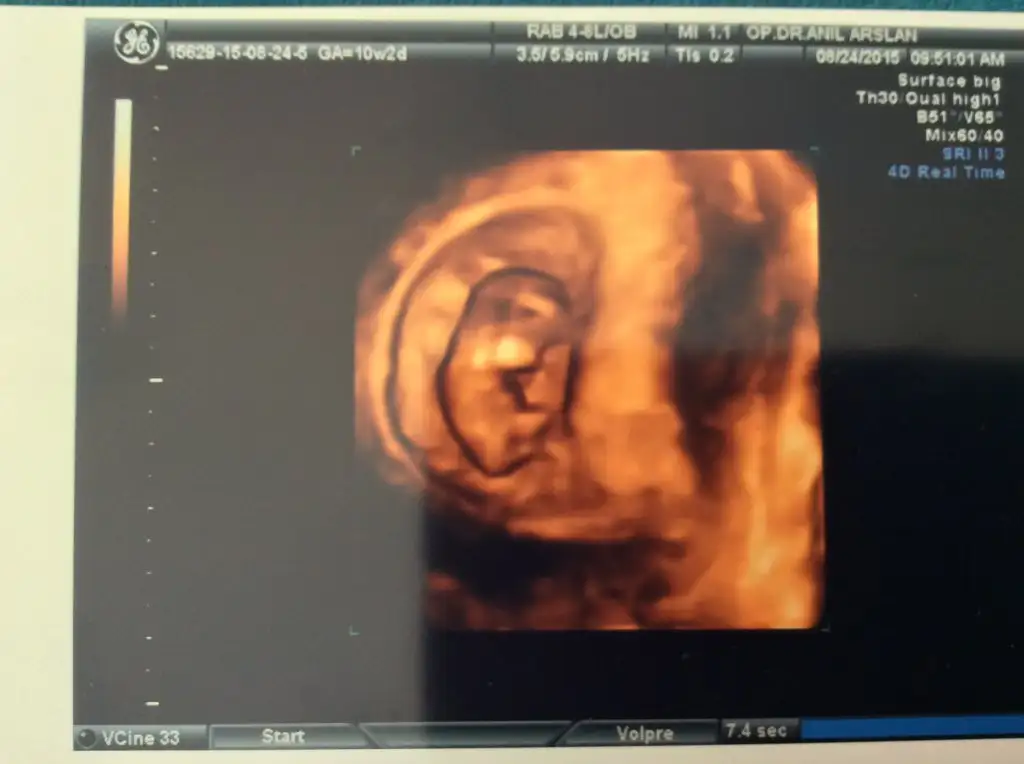

Herkese merhabaaaalar :) çok mutluyum randevumuz vardı bugün doktorumla :) bebişim tam 10 hafta 2 günlük :) adet tarihime göre de ultrasona göre de :) hiç bir problemimiz yok şu an Allah'a şükür... Allah'ım kimseye de dert vermesin.

3,5 cm olmuşuzkalbimiz kuş gibi atıyordu

9 gün sonra ikili teste gidicez inşallah